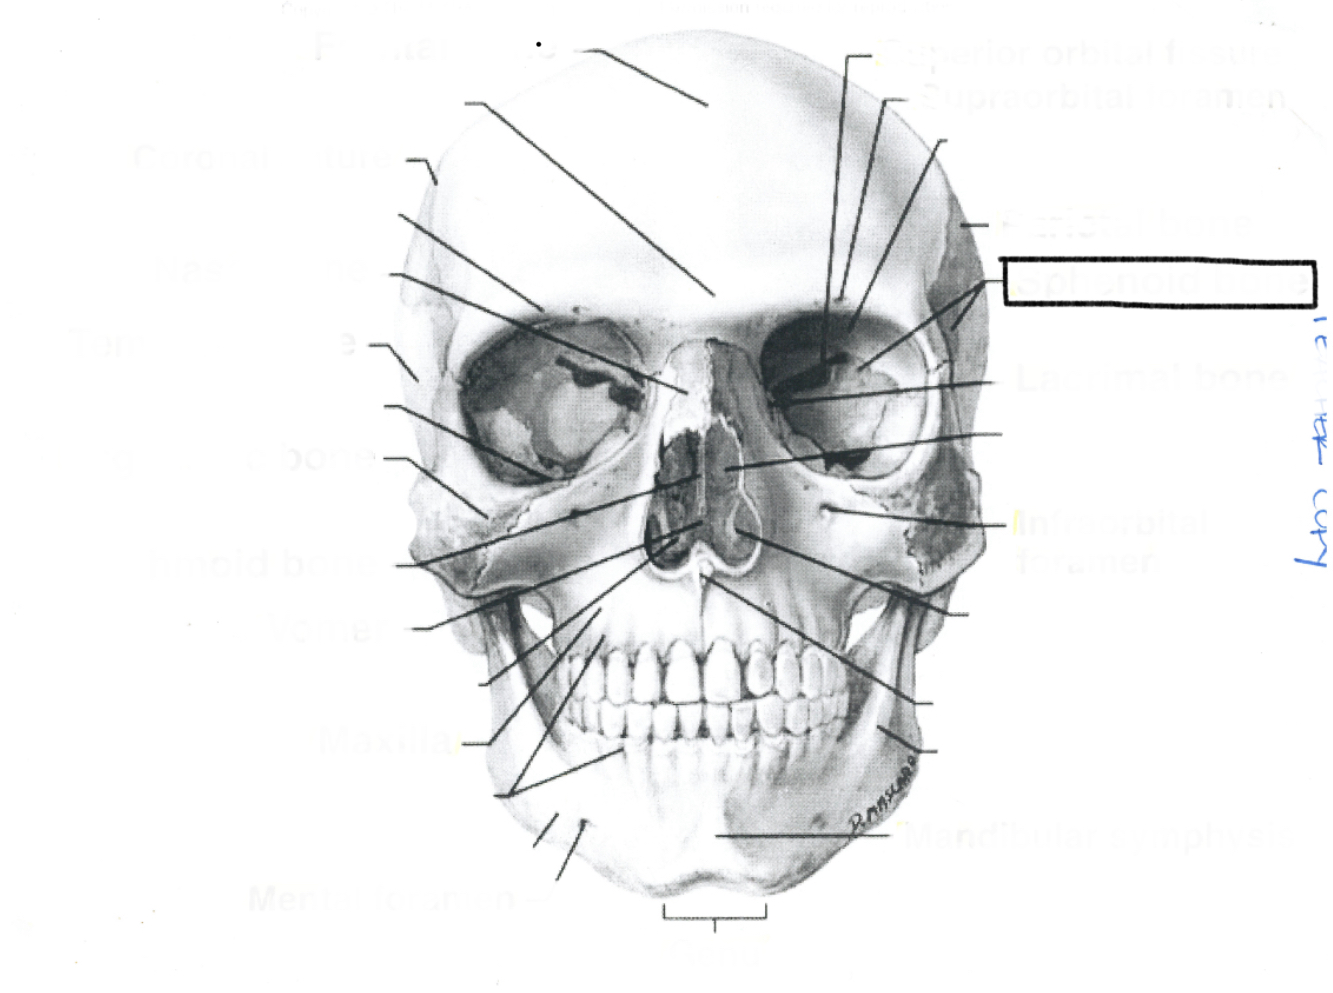

What is this?

What is this?

What is this?

What is this?

What is this?

What is this?

What is this?

What is this?

What is this?

What is this?

What is this?

What is this?

What is this?

What is this?

What is this?

What is this?

What is this?

What is this?

What is this?

What is this?

What is this?

What is this?

What is this?

What is this?

What is this?

What is this?

What is this?

What is this?